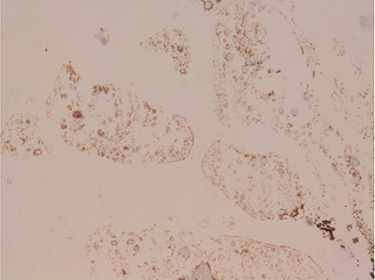

Microscopically, the tumour had ring-shaped tubules which were separated by stroma. The cells had small single nuclei and pale cytoplasm. Within the tubules, the cells were arranged in interconnecting configuration, and at the centre of each of these, there was a core of eosinophilic materials (Fig. 1). The nuclei of the cells were palisading both around the hyaline cores and at the periphery of the tubules. There was no necrosis and the capsule was free from the tumour. Both calretinin (Fig. 2) and inhibin (Fig. 3) were strongly positive, whereas cytokeratin AE1/AE3 (Fig. 4) was weakly positive. The diagnosis of SCTAT was confirmed. After 6 months, the patient’s mother was contacted and she reported no complaint regarding the condition of the patient.

Figure 4.

Staining of CK AE1/AE3: the tumour cells are weakly stained (IHC, ×40).